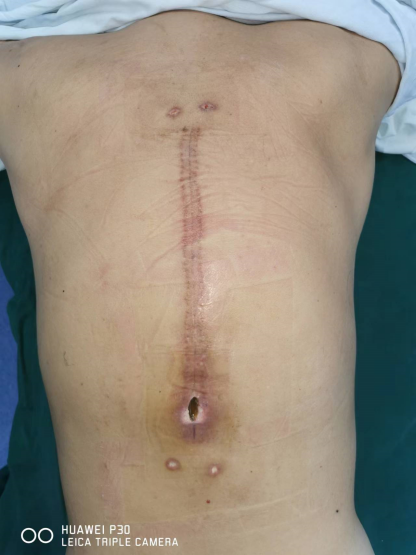

術后難愈性切口(超級耐藥)—Masquelet技術+NPWT